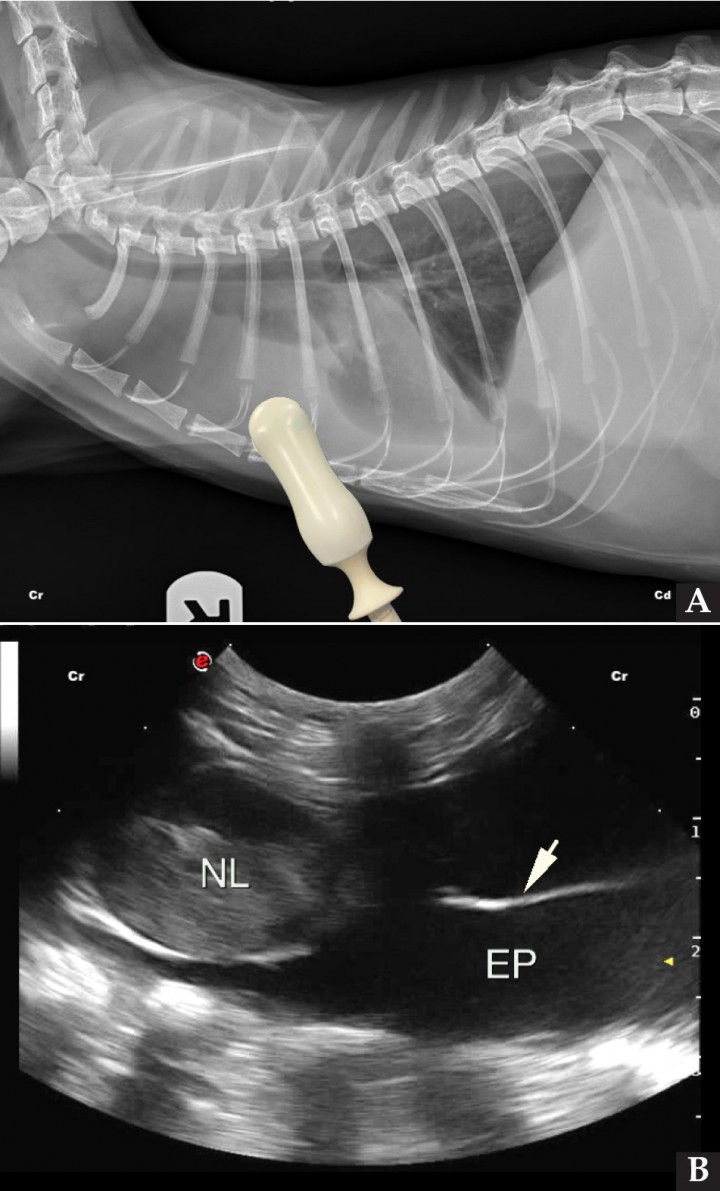

<p>(<strong>A</strong>) Radiografía de un gato con linfoma multicéntrico y efusión pleural severa, con la colocación de la sonda ecográfica en el punto de valoración del cuadrante PH. (<strong>B</strong>) Imagen ecográfica del mismo gato valorando el cuadrante PH, donde se puede observar un nódulo linfático esternal moderadamente aumentado de tamaño (NL), así como abundante contenido anecoico entre ambas pleuras, confirmando la presencia de efusión pleural (EP) y la presencia de fibrina fluctuando en el líquido pleural (flecha blanca). Cr: craneal; Cd: caudal.</p>

(A) Radiografía de un gato con linfoma multicéntrico y efusión pleural severa, con la colocación de la sonda ecográfica en el punto de valoración del cuadrante PH. (B) Imagen ecográfica del mismo gato valorando el cuadrante PH, donde se puede observar un nódulo linfático esternal moderadamente aumentado de tamaño (NL), así como abundante contenido anecoico entre ambas pleuras, confirmando la presencia de efusión pleural (EP) y la presencia de fibrina fluctuando en el líquido pleural (flecha blanca). Cr: craneal; Cd: caudal.